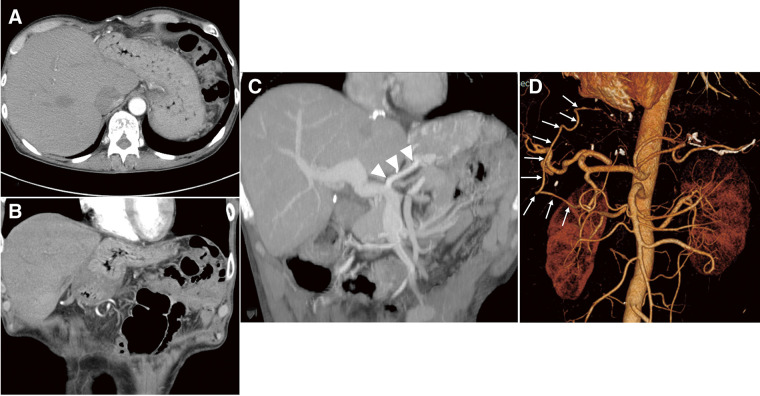

The malignancy risk has increased following improvements in the long-term survival rates after liver transplantation. Reports show a 23.4-fold increase in the risk of de novo esophageal cancer after liver transplantation compared to the general population. We report the case of a 47-year-old female diagnosed with early esophageal cancer after liver transplantation. Endoscopic submucosal dissection was performed; however, due to it being a noncurative resection, additional treatment was required. Total robot-assisted minimally invasive esophagectomy (RAMIE) was performed using a robot for thoracic and abdominal procedures. Although extensive adhesions were observed after liver transplantation, precise surgery using the robot did not damage any vital organs, such as the graft blood vessels. The patient was discharged without postoperative complications. Total RAMIE for esophageal cancer after liver transplantation is a feasible and safe option following careful evaluation of the patient's condition, and expands the possibilities of successful complex posttransplant surgeries through robotic precision.